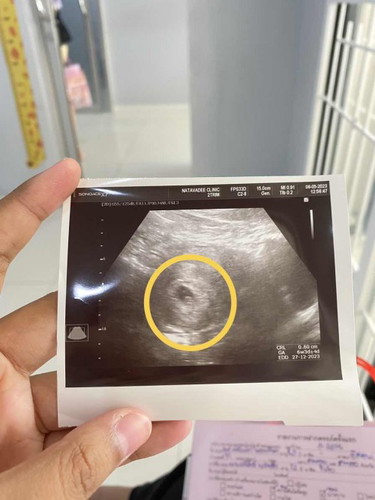

แม่ๆคะ แบบนี้คือเจอน้องแล้วใช่ไมคะ

หมอบอกท้องอ่อนๆ ได้1เดือนกว่าๆคะ 6 week 4d เราดูไม่ออกเลยคะว่าน้องอยู่ตรงไหน ตอนนั้นดีใจมากคะ ไม่ได้ถามอะไรหมอเลยคะ เอาแต่ชื่นชมภาพน้องคะ แต่ในใจก็เอะดูไม่ออกเอาแต่ดีใจอยู่คะ ( ตอนนี้ปวดท้องหน่วงๆคะ จะเป็นอะไรไมคะ )

ยังเป็นแค่ถุงตั้งครรภ์ค่ะ ต้องเขาถึงวีคที่ 8 ค่ะ ถึงจะเห็นชัด ของเรา 8 วีค น้องเริ่มเป็นตัวอ่อนและมีหัวใจแล้วค่ะ ตอนนี้ 10 วีค 4 วัน แล้วค่ะ คุณแม่ชอบนอนจับท้องตัวเองค่ะ ความรู้สึกเหมือนได้สัมผัสลูกในท้อง

ของเราก็เจอแบบนี้ค่ะไปหาหมอตอน5wเจอแบบนี้เลยข้างในถุงทารกเล็กมากยังเท่ากับเมล็ดงาอยู่เลยค่ะเดี๋ยวน้องก็โตพัฒนาขึ้นเรื่อยๆนะคะคุณแม่

ตอนเรา 6w1d น้องก็แค่ 4 มิลค่ะ มีเสียงหัวใจเต้น เห็นใบซาวของแม่ 6 มิล ไม่ต้องกังวลนะคะ หมอนัดเราอีกสองอาทิตย์ ไปซาวอีกทีน้องตัวโต 2 เซ็น เลยค่ะ

ซาวด์ช่องคลอดค่ะ จะเห็นเป็นประมาณนี้ แต่ถ้าซาวด์ท้อง แทบจะไม่เห็นถุงการตั้งครรภ์ด้วยซ้ำ (แม่พุงเยอะด้วยมั้งคะ 555)

บ้านนี้คือเห็นชัดเลยค่ะ ตอน 7+4 วีคทั้งน้องพร้อมหัวใจ แม่รออีกหน่อยนะคะ เดี๋ยวก็เห็นน้องชัดๆ ค่ะ ช่วง 8-10 วีคค่ะ